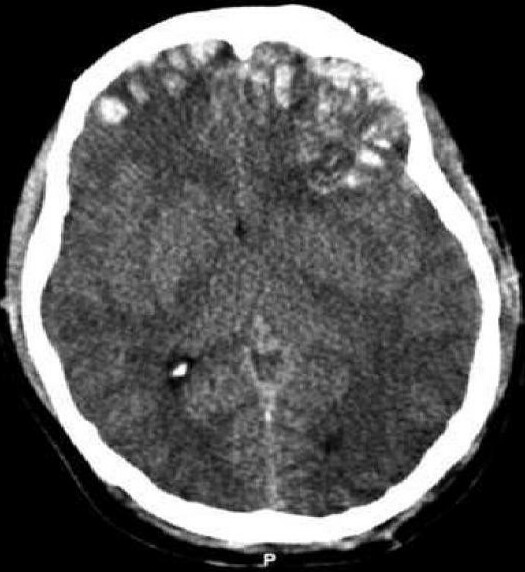

CT-scan of a frontal intracerebral hemorrhage on the right (left image side) as a contre coup. There is dens suture material visible left occipital in the skin.

Brain trauma CT. - Primary brain injuries, Secondary brain injuries